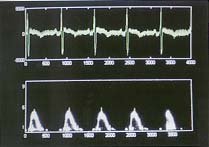

音频处理系统检查 在超声心动图检查时,将血流的音频信号及心电信号同步输入计算机,经机内音频处理模块、实时声谱模块、自动识别模块分析、处理后,按改良肺动脉/主动脉血流时间间期比法自动估测肺动脉收缩压(PASPA)、平均压(PAMPA),显示、打印并储存结果(图1,2)。

(频谱上的黄线为自动识别模块识别的特征点)

图2 音频系统采集的心电图信号及肺动脉血流的音频信号